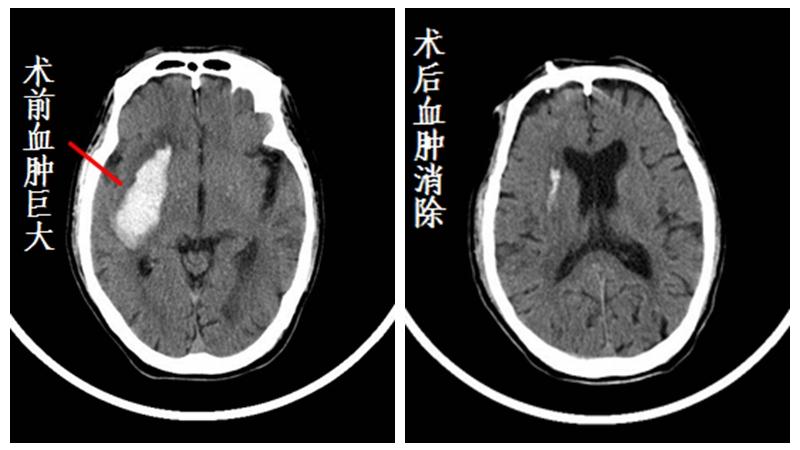

62岁的老章被送到急诊的时候,情况很不妙:血压180/100毫米汞柱,高得吓人,昏迷样、意识模糊、不能站立和言语,右侧肢体偏瘫,经过急诊CT显示,老章脑中线偏移明显,左脑基底节区一个硕大的血肿,约有40毫升出血,相当于半杯葡萄酒的容量。

老章被推进了手术室,医生施以局部麻醉,在颅骨上开一个仅筷子粗的微小创口,利用导向仪,将一根带有刻度的硅胶引流软管从脑少血管区直接进入病灶,术中即可进行部分引流减压。手术过程不到30分钟。术后,老章被转入病房继续输注血肿溶解药物进行引流。次日,老章恢复清醒,对话无碍,手脚能动,已经能配合医护人员做术后的康复治疗。两天后,脑部的淤血被引流干净,一周后出院。经过一年半的复查,目前老章仅需按时吃降压药,就能维持很好的生活质量。